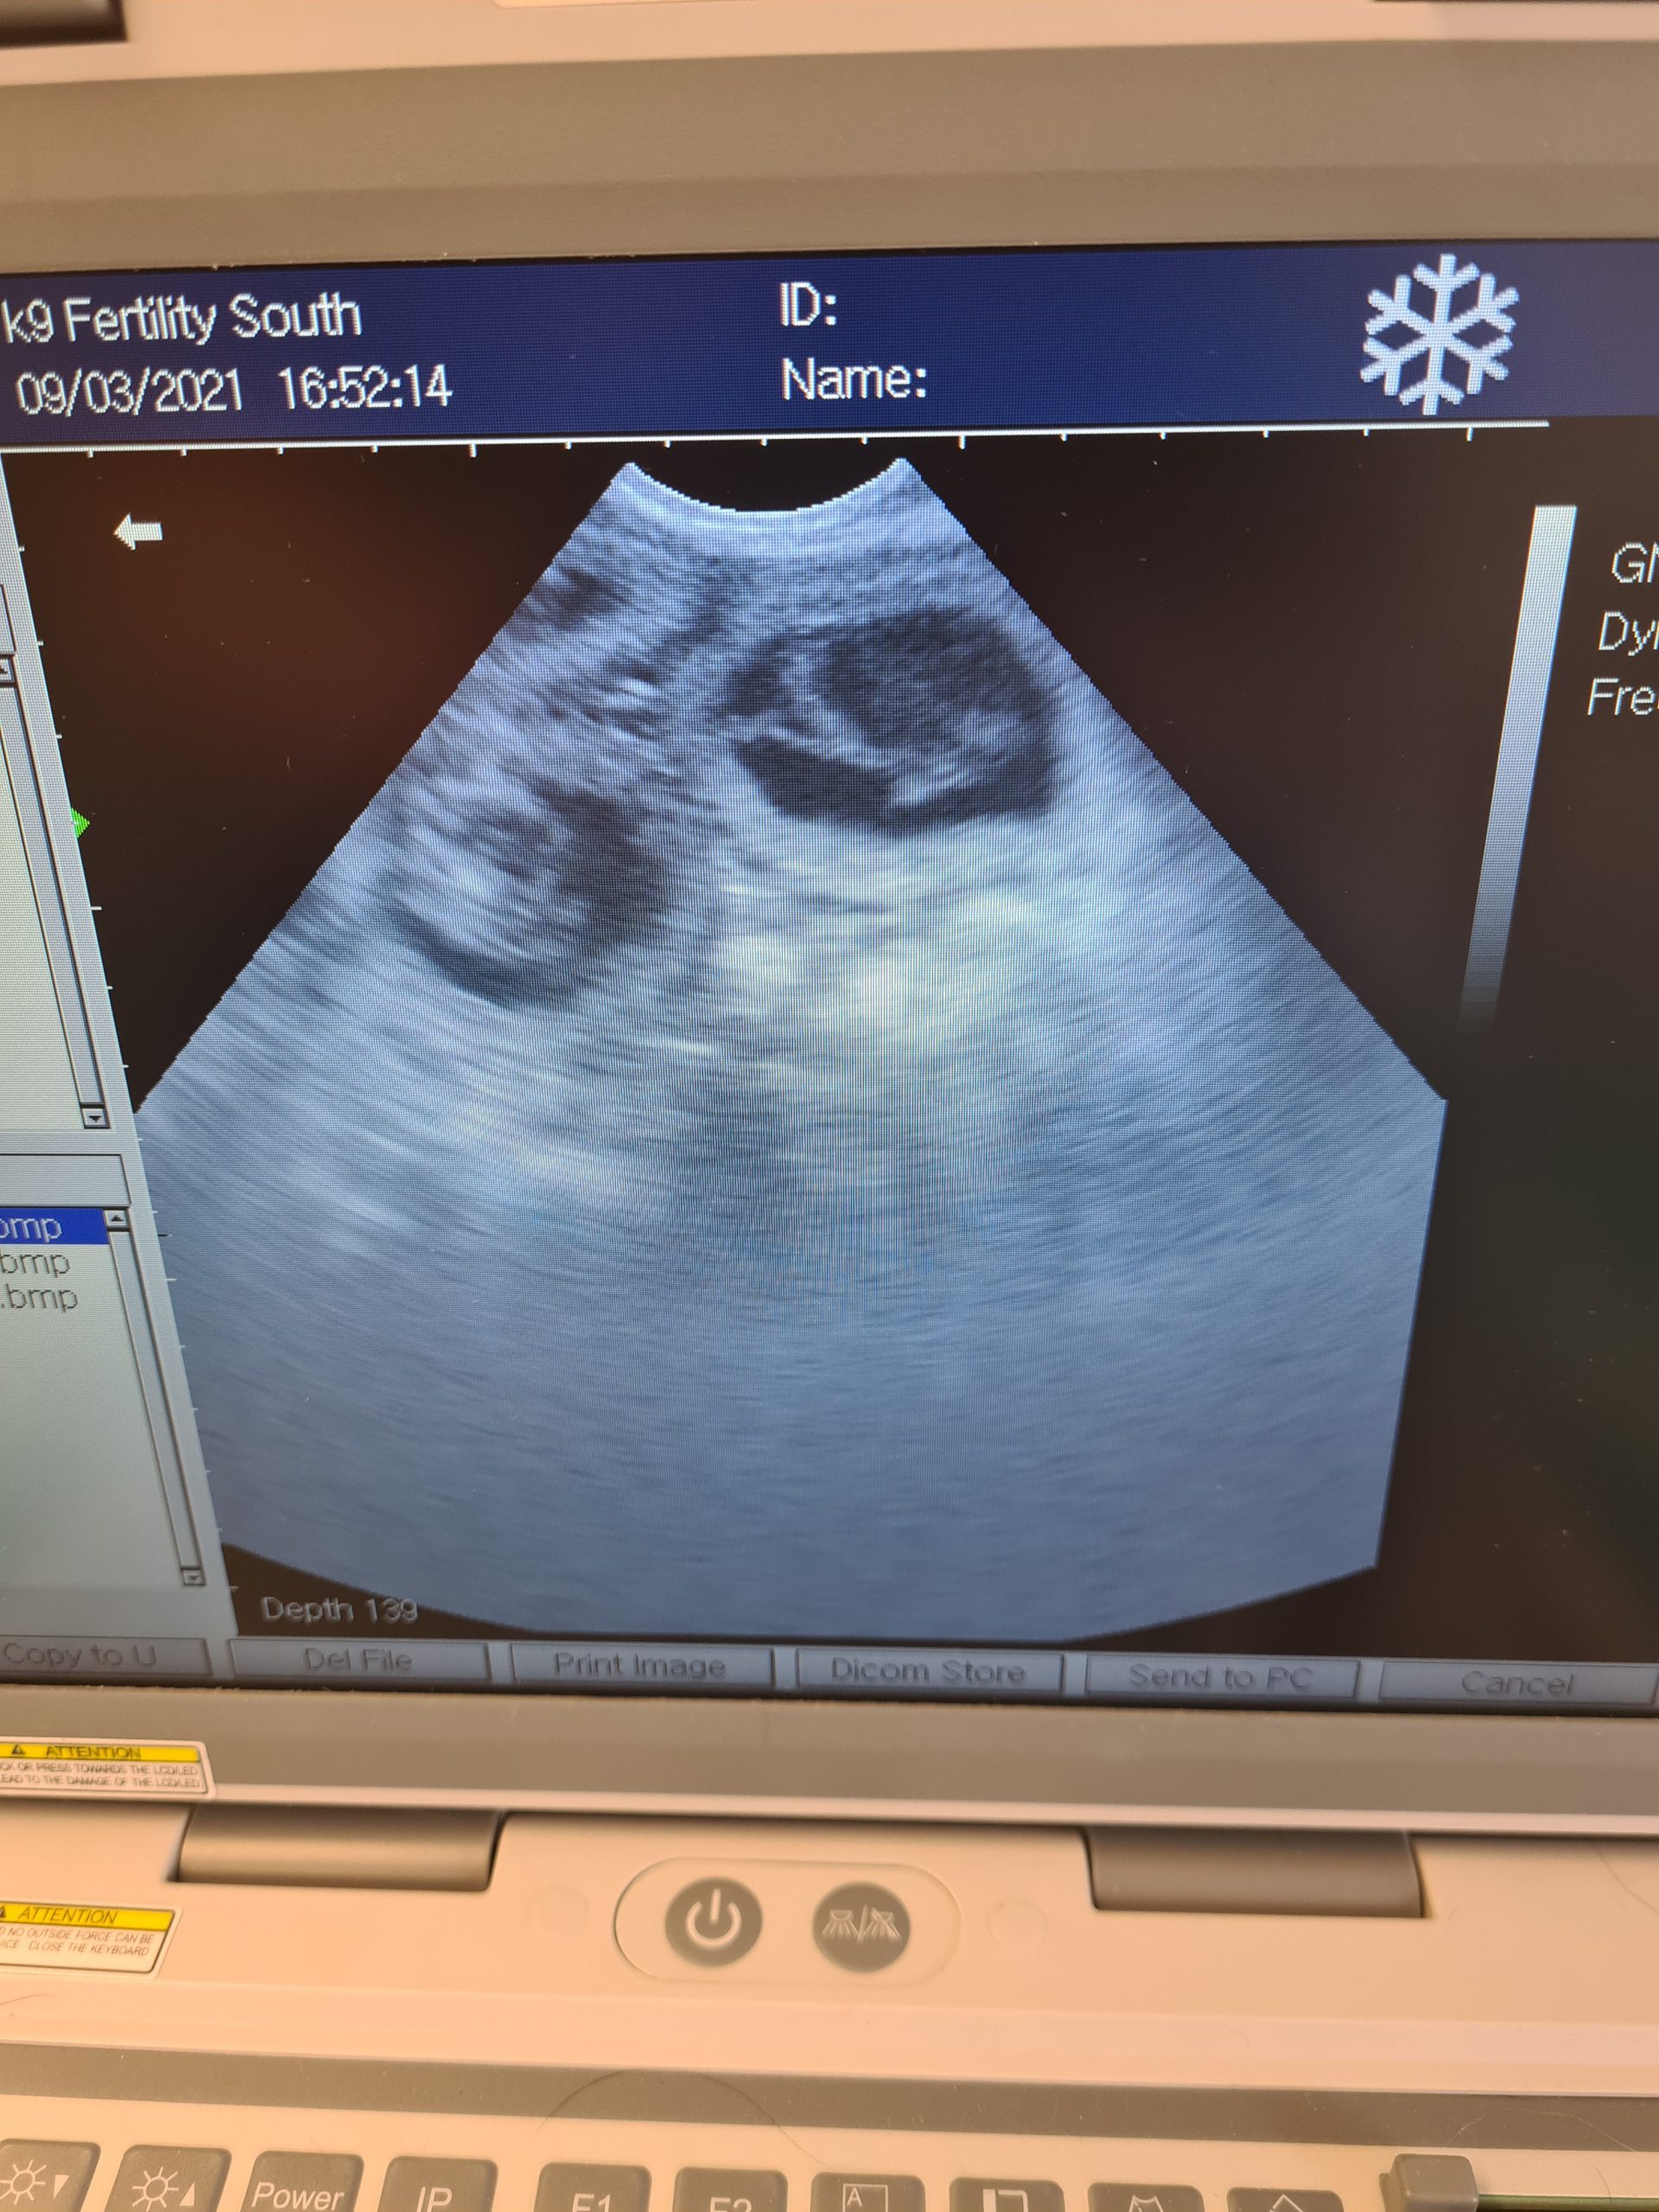

Daschund and Maltese scans following cytology and a.i. here at the clinic

Day 32 5 pups seen